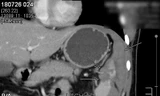

Suýt chết vì nghẹn miếng thịt heo 5cm kẹt trong thực quản ảnh 1Hình ảnh khối dị vật trong thực quản bệnh nhân

Sáng ngày 17/8 bệnh nhân N.V.H được đưa vào nhập viện tại Bệnh viện Đa khoa Tư nhân Bình Dương, ê kíp bác sĩ sau khi thăm khám và thực hiện cận lâm sàng đã xác định phần thức ăn bị vướng tại 1/3 dưới thực quản của người bệnh này.